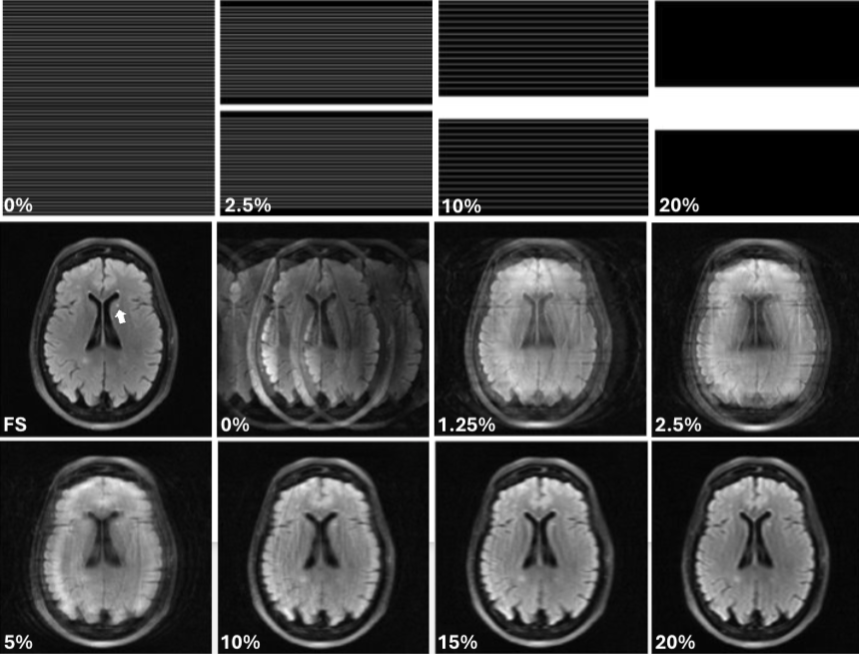

Modeling human observer performance with neural network observers in a forced localization task using undersampled MRI images

SPIE Medical Imaging | NIH R15-EB029172

Built FLNet (EfficientNet-B1 variant) for tumor localization under MRI undersampling artifacts, trained on 8,240 images spanning multiple artifact regimes. Developed a vision-inspired variant using Gabor-based preprocessing to better match human perception. Achieved 84% accuracy (vs. humans 82% and SDOG4 68%) and improved generalization to extreme / out-of-distribution artifact conditions.